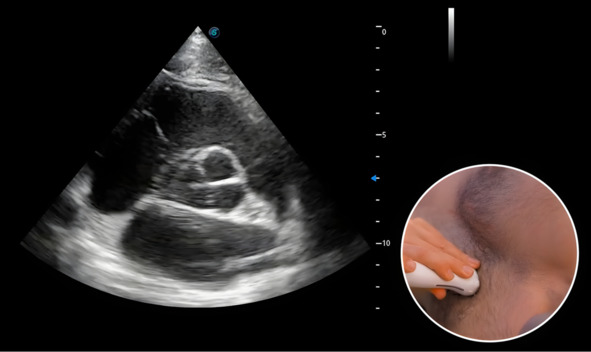

Для смены позиции необходимо снова вывести парастернальную позицию по длинной оси левого желудочка, а затем повернуть датчик по часовой стрелке (рис. 6).

Рис. 6